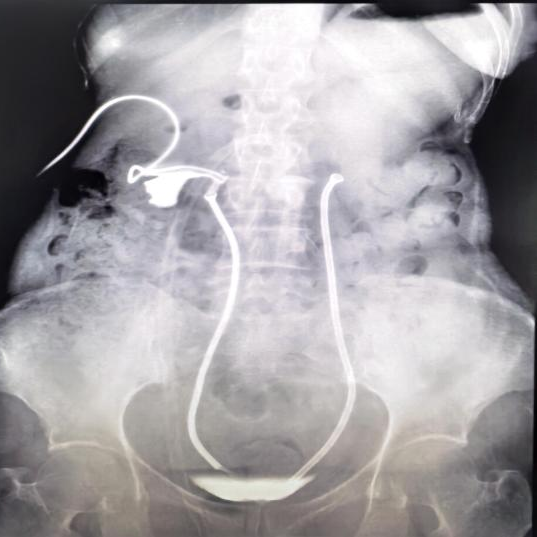

术后复查影像显示患者肾积水明显减轻,尿液引流通畅

术后,阳女士的肾功能得到显著改善,在夹闭肾造瘘管的情况下,肌酐值从术前的168.7umol/L降至正常范围。后续影像复查确认,尿液已能经由温控支架架构的“新通道”顺畅流入膀胱。最终,阳女士在出院前成功拔除了困扰她已久的肾造瘘管。